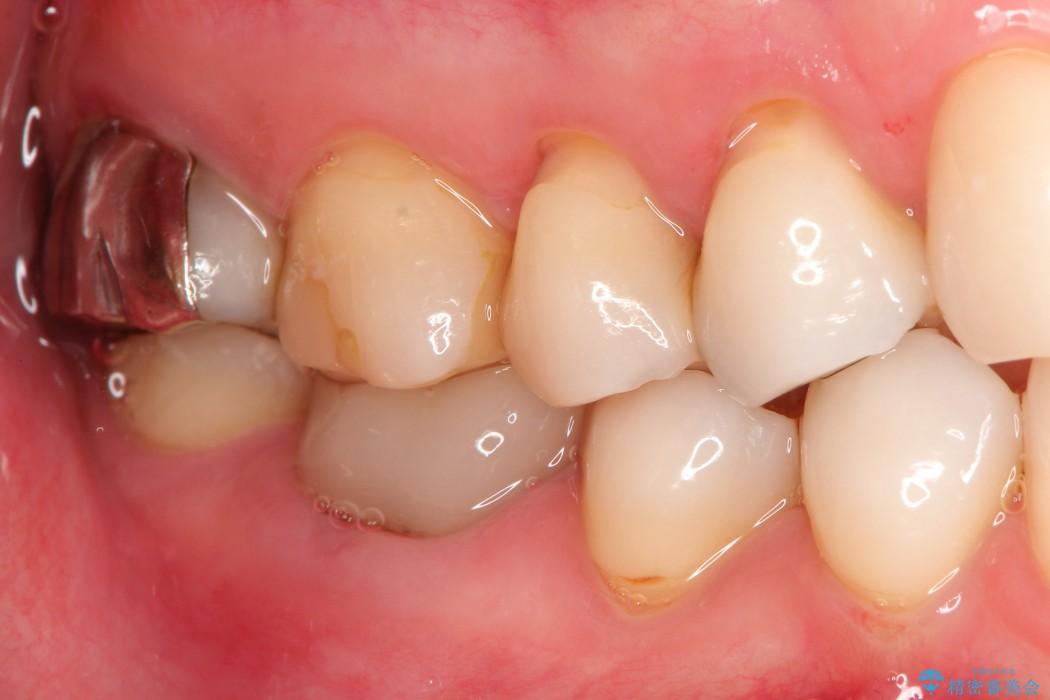

治療後について

抜歯を行った当日に骨の維持をする為、人工の骨を充填しました。インプラントを埋入する際には、ほとんどが自分の骨に置き換わっており、頬舌的なへこみを引き起こす事もなく、審美性・機能性ともに維持する事が出来ました。

また今回の治療では「バイコンインプラント」を使用する事により、インプラントの土台とセラミッククラウンを付ける際にセメントが全く残らないという利点を生かしたところ、見た目にも綺麗に仕上がり、患者様にも喜んでいただきました。

※下あごのインプラント治療の場合、ネジで止めるインプラントでは「ネジ止め用の穴」が少し見えてしまい審美性に欠けるデメリットがあります